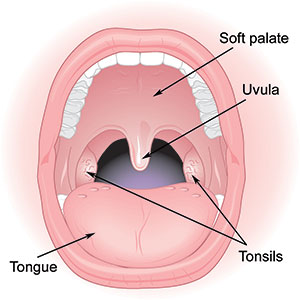

Overview

Package includes:

Days in hospital : 2 to 3 Days (For patient and one attendant)

Days in hotel : 5 Days (For patient and one attendant)

Room type in hospital : Shared

Room type in hotel : Private

Hotel category: Standard

Value added benefits of the Tonsillectomy: